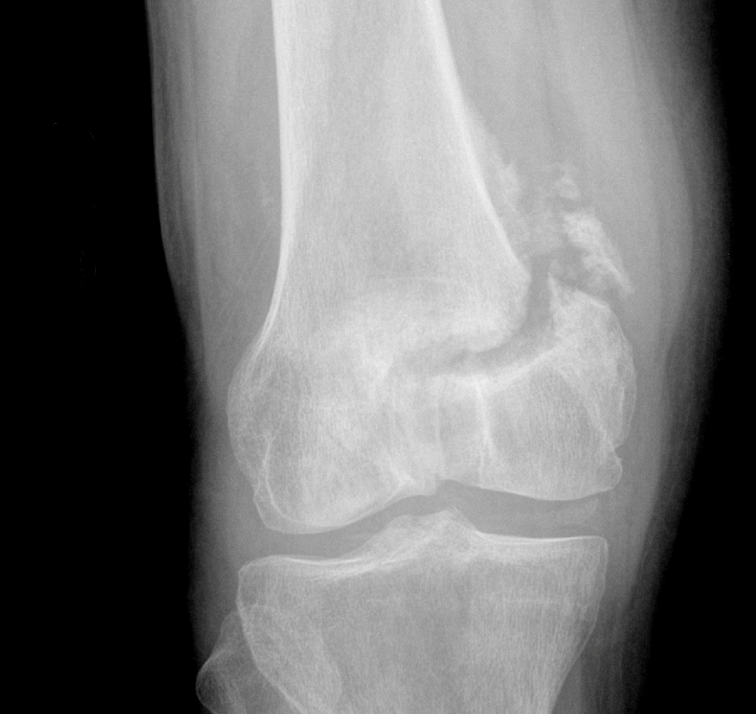

A 54-year-old man injured his leg in 2011. He was treated non-operatively, but two years later the pain had only grown worse. He also had a worsening deformity of his knee.

By 2013, he'd had enough. He came to see Dr. Stoneback at University of Colorado Hospital, where the team took a comprehensive look at his health. Dr. Stoneback saw that the broken bone had affected the nearby joint, creating an angular deformity and

making it particularly difficult to treat.